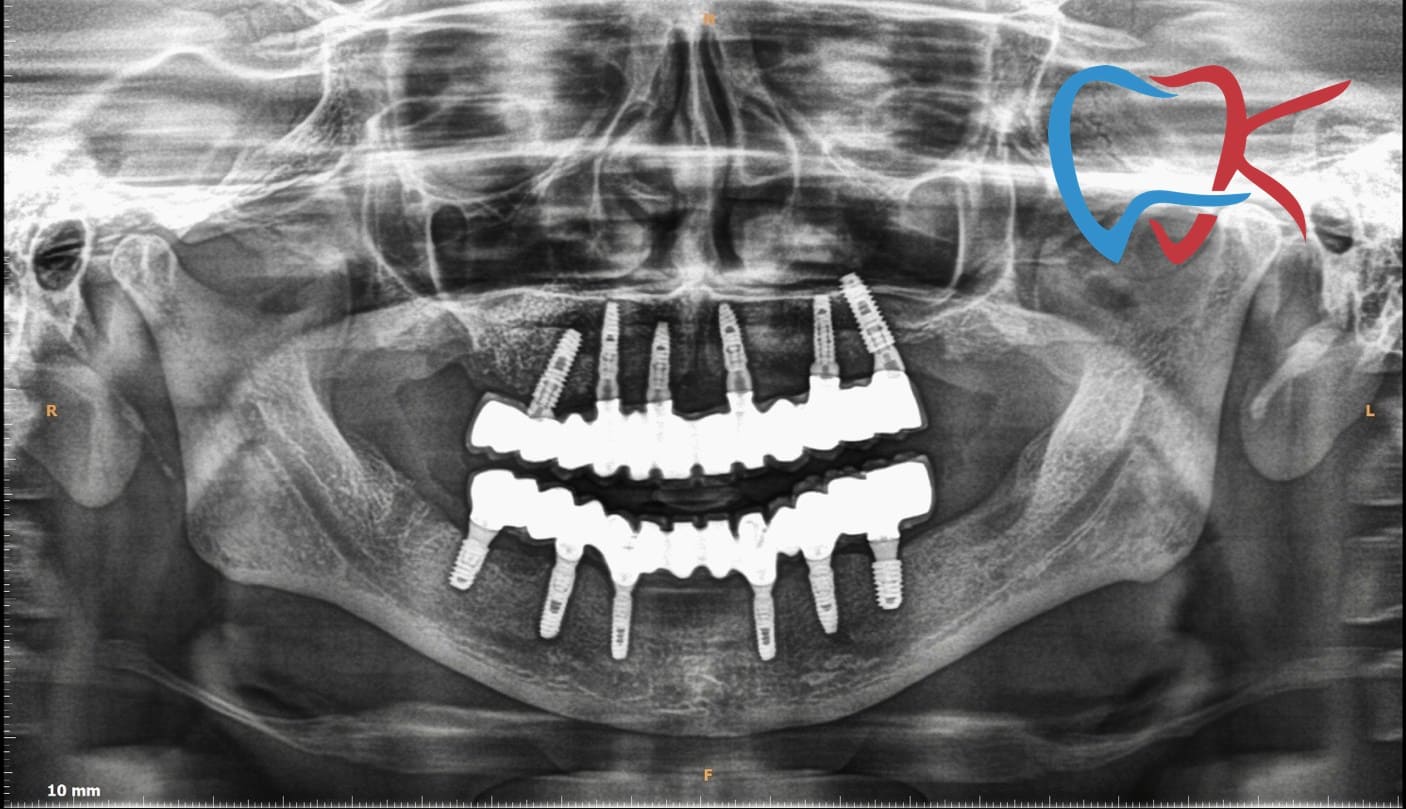

Digital-Xray

Digital radiography is a key development in diagnostic imaging that can help improve patient care, support better patient outcomes, expand consultation capabilities, and enhance client interaction.